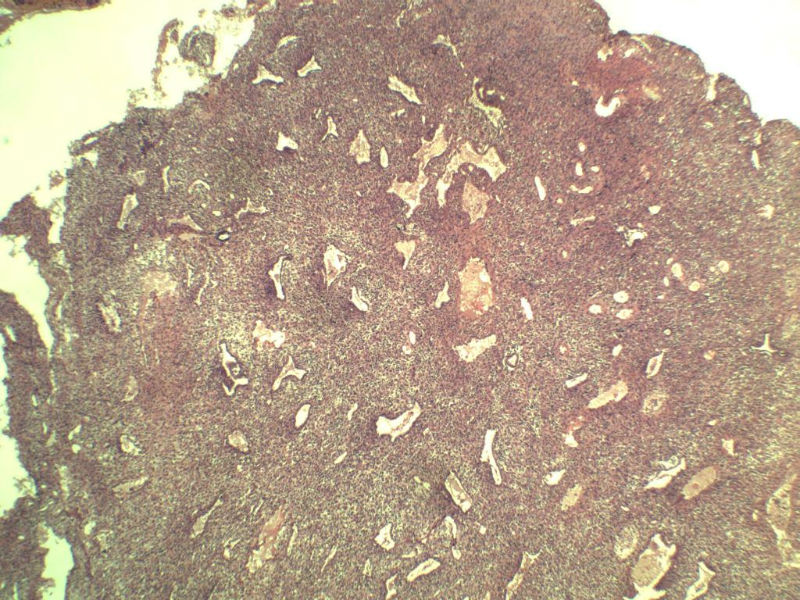

这是另外一个 40岁 经期延长 流血量增多 半年 这是蜕膜样变吧 有什么意义吗? 要报告不?